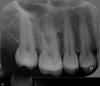

Korn05 Опубликовано 13 июля, 2013 Поделиться Опубликовано 13 июля, 2013 Год назад была поставлена пломба (довольно глубокая) на больной зуб - после этого целый год с зубом все было хорошо.Недавно, после того как был установлен имплант на противоположной стороне рта, и пришлось чаще жевать этим зубом с пломбой (чтобы не задевать имплант лишний раз), этот зуб опять начал побаливать. Боль почти постоянная, хоть и не сильная, кажется что находится в глубине зуба. Не знаю, связано ли с имплантов возобновление боли. Был у трех независимых врачей в двух разных странах. Каждый из них сделал рентген зуба, и каждый сказал, что судя по рентгену и внешнему виду зуба, все ок, в чем проблема - они не знают. Один врач просто посоветовал чистить зубы пастой для чувствительных зубов и поменьше жевать этой стороной. Другой сказал, что "возможно" на зубе трещина, и "возможно" надо ставить коронку, чтобы он перестал болеть. Но при этом никакой трещины не нашел. В общем, никто ничего не знает. А зуб продолжает болеть. Я сейчас временно проживаю в стране со слабо развитой стоматологией- тут даже нет возможности сделать панорамный снимок зубов, скорей всего. Можно поставить пломбу, коронку, и т.д. Можно сделать самое простое. Каналы лечат, но наверняка очень плохо. Пожалуйста, подскажите, в чем может быть причина боли, что необходимо сделать. Моежт быть, заменить пломбу? Какие действия можно предпринять, чтобы выяснить причину боли? В Россию я не смогу поехать в ближайший год в связи с работой тут, не хотелось бы год прожить с больным зубом, нужно предпринять какие-то действия уже сейчас. Снимок прикрепил. Зуб, о котором идет речь - 6-ка, самый большой на снимке (2-ой слева), основной жевательный. Ссылка на комментарий

Scrabble Опубликовано 13 июля, 2013 Поделиться Опубликовано 13 июля, 2013 По снимку вообще ничего плохого-и пломба от полости зуба далеко. 1 Ссылка на комментарий

Alisa st Опубликовано 15 июля, 2013 Поделиться Опубликовано 15 июля, 2013 Судя по снимку, зуб выдвинут вниз,скорее всего оголена шейка и поэтому зуб реагирует. Опишите подробнее характер болей-постоянная или вызывается какими-то раздразжителями и тд Ссылка на комментарий

Magdalena Опубликовано 15 июля, 2013 Поделиться Опубликовано 15 июля, 2013 А между зубами пища не застревает? Десна не кровоточит? Вы давно делали профгигиену? Видно зубной камень в межзубном промежутке 16-17, на 17.Проводили холодовой тест? Ссылка на комментарий